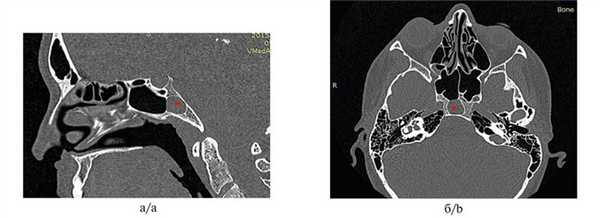

Пациентка Н., 32 года, обратилась в клинику с жалобами на головную боль, периодически сопровождающуюся головокружениями, двоением в глазах, слабостью и повышением температуры тела до субфебрильной. Впервые жалобы появились около 1 года назад. Пациентка неоднократно обращалась к специалистам разного профиля, однако назначаемое лечение положительного эффекта не имело. При эндоскопии ЛОР-органов: слизистая оболочка носа бледно-розовая, влажная, блестящая, нижние носовые раковины увеличены в объеме, хорошо сокращаются при анемизации, перегородка носа искривлена вправо в виде шипа, контактирующего со средней носовой раковиной. Носовое дыхание удовлетворительное. Обоняние не нарушено. Со стороны других ЛОР-органов патологии не выявлено. На компьютерной томограмме околоносовых пазух определяются пристеночное снижение пневматизации клиновидной пазухи, наличие кармана с достаточно тонкой стенкой, граничащей с задней черепной ямкой (рис. 1), Рис. 1. Компьютерная томограмма околоносовых пазух пациентки Н. до операции: сагиттальная (а) и аксиальная (б) проекции. Fig. 1. Computed tomography of the paranasal sinuses of patient N. before surgery: sagittal (а) and axial (b) projections. Определяются выраженный затылочный карман, заполненный патологической тканью (обозначено звездочкой), и тонкая задняя стенка пазухи, граничащая с задней черепной ямкой. The fairly well visualized occipital pocket (indicated by the asterisk) and the thin posterior wall of the sinus bordering the posterior cranial fossa. искривление перегородки носа. На основании результатов обследования был поставлен диагноз: хронический сфеноидит. Кистоподобное образование клиновидной пазухи.

Под общей анестезией в условиях искусственной вентиляции легких с использованием электромагнитной навигационной станции Fusion (фирма «Medtronic», США) были выполнены септопластика и эндоскопическая трансназальная сфенотомия. Навигационная техника использовалась для точного позиционирования места перфорации передней стенки клиновидной пазухи, что в данном случае было актуально из-за особенностей ее анатомии. Расширение естественного соустья выполняли бором с автоматическим орошением и каналом для аспирации, что позволило достаточно быстро и безопасно вскрыть пазуху. При ревизии полости клиновидной пазухи с помощью эндоскопов 45° и 0° определялась неизмененная слизистая оболочка. Использование навигационной станции позволило точно визуализировать расположение предполагаемой кисты (рис. 2). Рис. 2. Пациентка Н. Интраоперационная визуализация (данные с монитора навигационной станции) позволила хирургу с высокой точностью определить локализацию патологического процесса (обозначено звездочкой). Fig. 2. Patient N. The intraoperative visualization (available at the monitor of the navigation station) enabled the surgeon to accurately locate the pathological process (indicated by the asterisk). Она локализовалась в отдельной ячейке (в затылочном кармане), сообщающейся с пазухой отверстием до 7 мм в диаметре. При удалении киста опорожнилась, содержимое — густой гной.